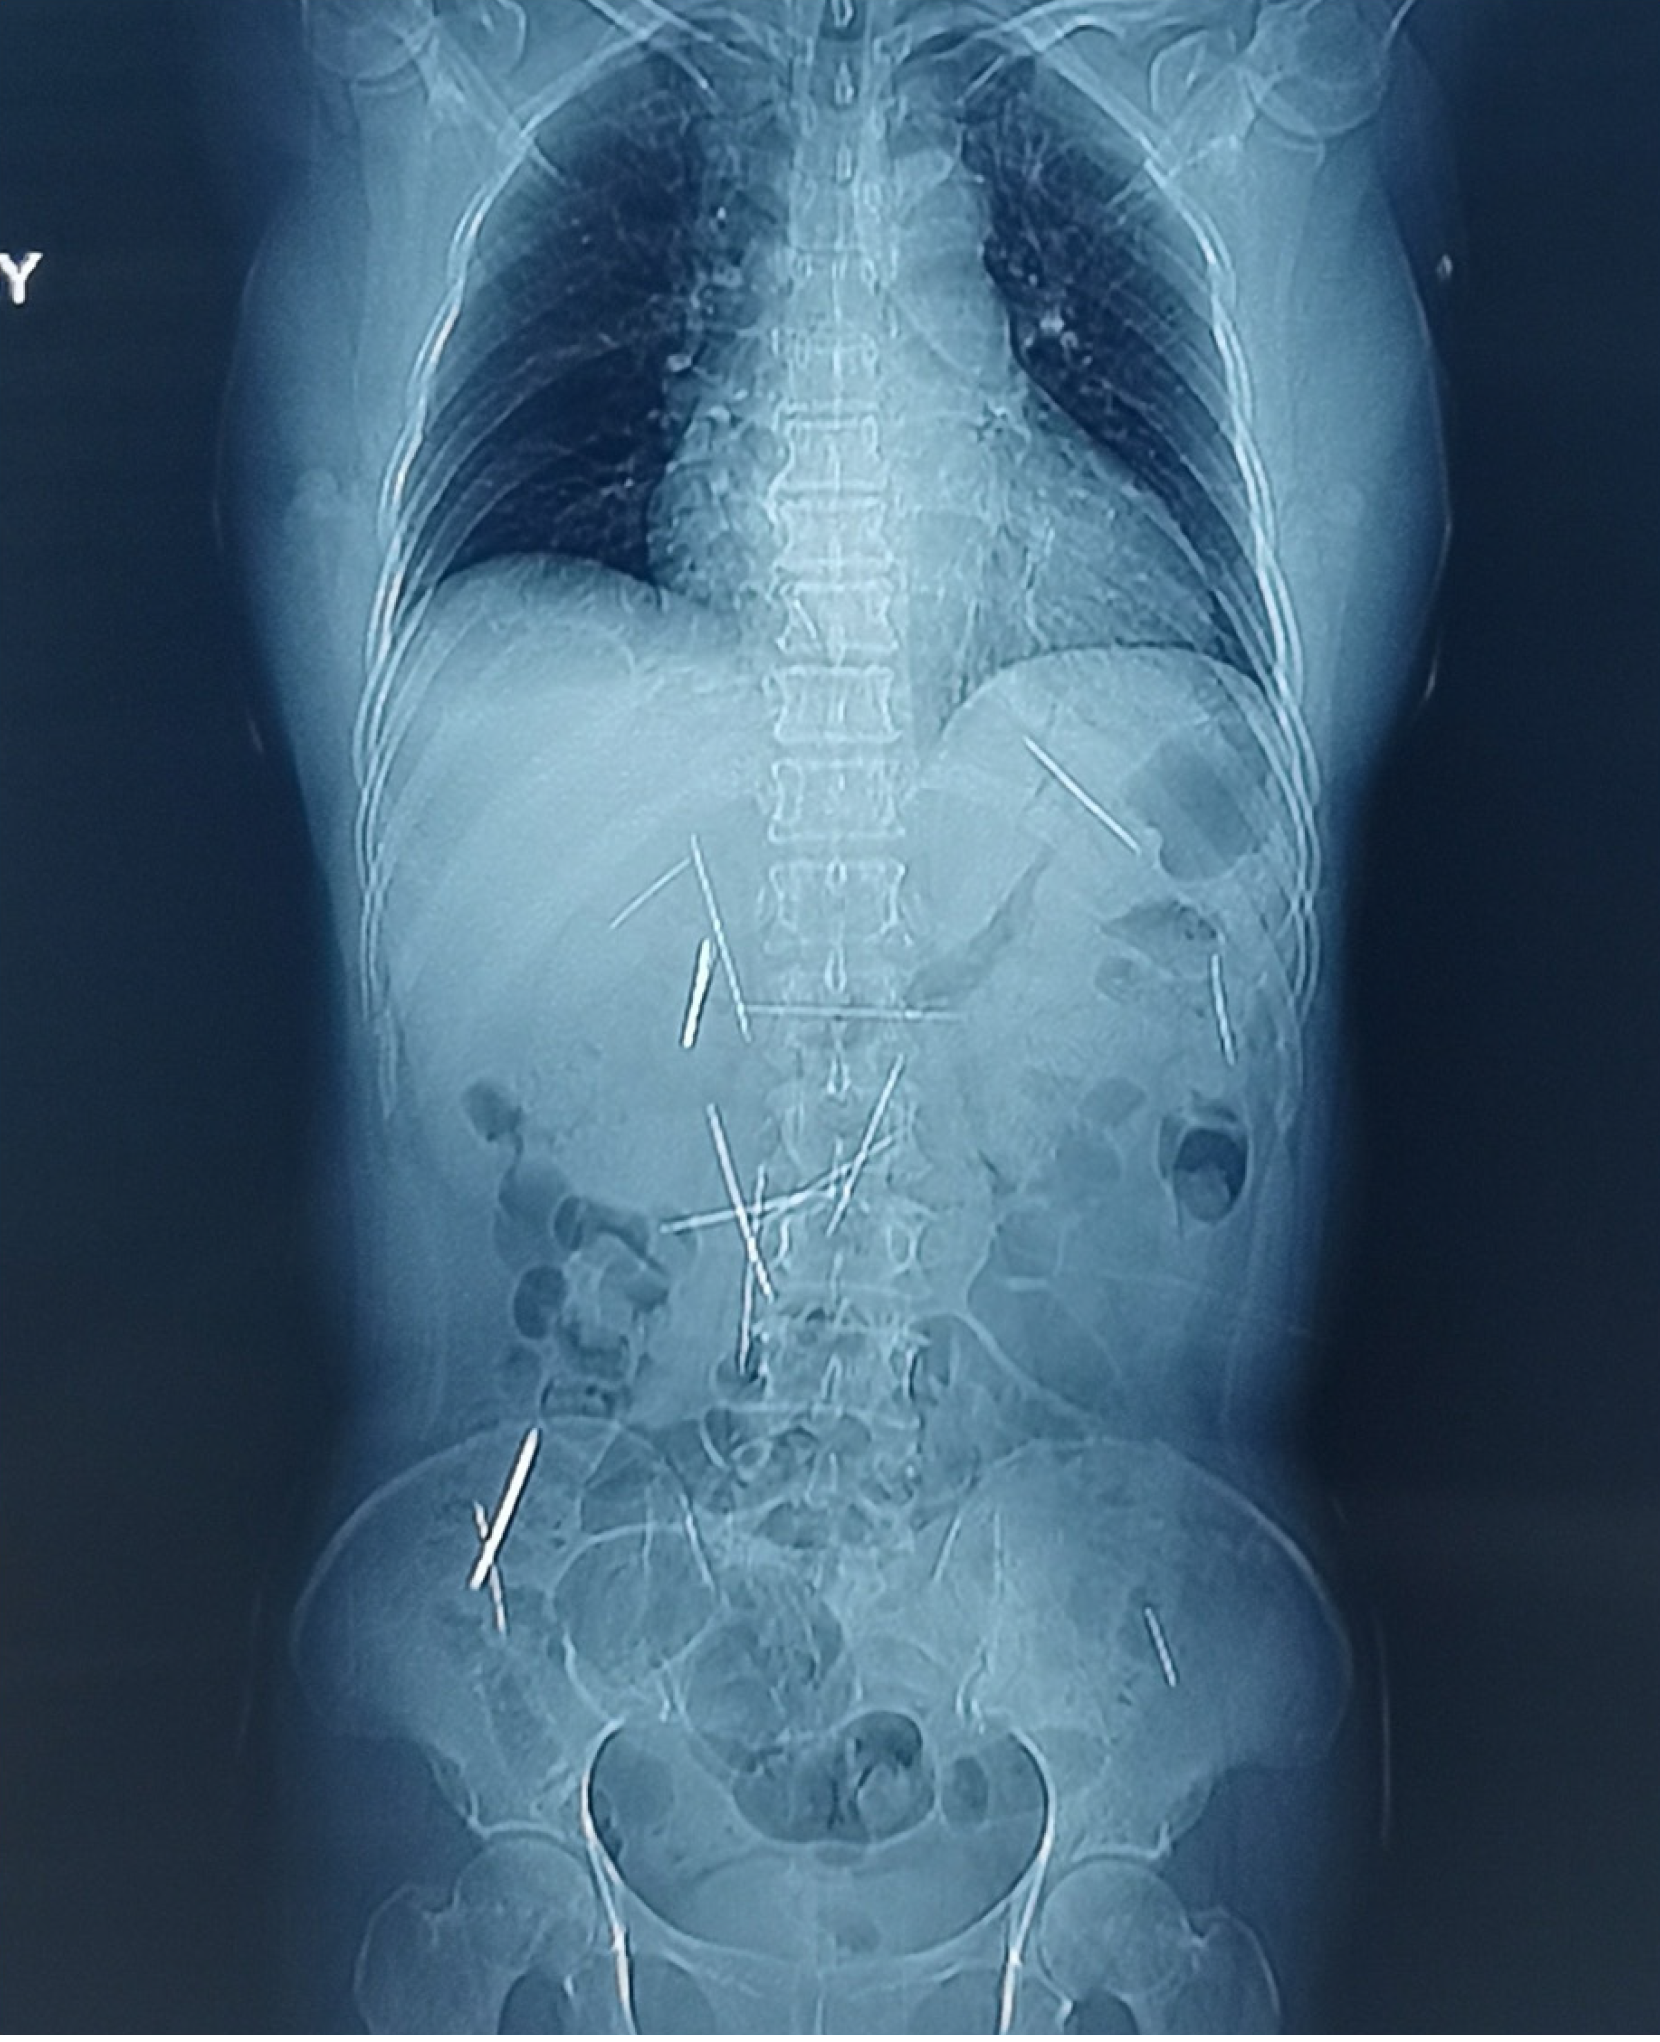

Figure 1 Preoperative abdominal radiography demonstrating multiple metallic foreign bodies distributed in the abdominal cavity.